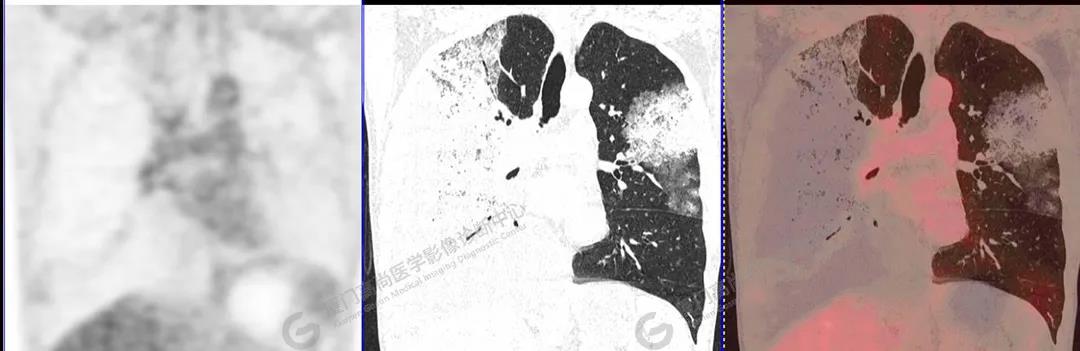

PET/CT影像圖

圖10

PET/CT所見(jiàn):雙肺大片實(shí)變影及磨玻璃影,部分呈地圖樣改變,累及右肺尖,部分放射性攝取輕微增高,SUVmax 1.77,其內(nèi)見(jiàn)多發(fā)支氣管充氣征象。

影像診斷: 雙肺大片實(shí)變影及磨玻璃影,大部分代謝不高,局部代謝輕微增高,考慮肺泡蛋白沉積癥,建議病理學(xué)檢查或肺泡灌洗物檢查。

影像學(xué)表現(xiàn):HRCT上雙肺斑片影,以肺門為中心呈蝶翼狀對(duì)稱分布;病變可隨機(jī)分布在中央?yún)^(qū)、周圍區(qū)或全肺葉,病灶與正常分組織分界清楚,呈典型“地圖樣”改變;有支氣管充氣征,但表現(xiàn)為充氣支氣管細(xì)小且數(shù)量及分布稀少;“碎石路”征由彌漫性磨玻璃影及內(nèi)部網(wǎng)格樣小葉間隔增厚組成(鋪路石樣表現(xiàn))。無(wú)空洞、蜂窩狀改變、淋巴結(jié)腫大、胸腔積液及明顯實(shí)變等。肺內(nèi)病灶累及范圍、磨玻璃密度高低與PAP患者的病情嚴(yán)重程度相關(guān),嚴(yán)重者病灶累及全肺,同時(shí)出現(xiàn)肺內(nèi)大片實(shí)變,并見(jiàn)充氣支氣管征象。PAP影像學(xué)表現(xiàn)程度與臨床癥狀、體征嚴(yán)重程度不成比例,表現(xiàn)為影像改變重,臨床癥狀輕。